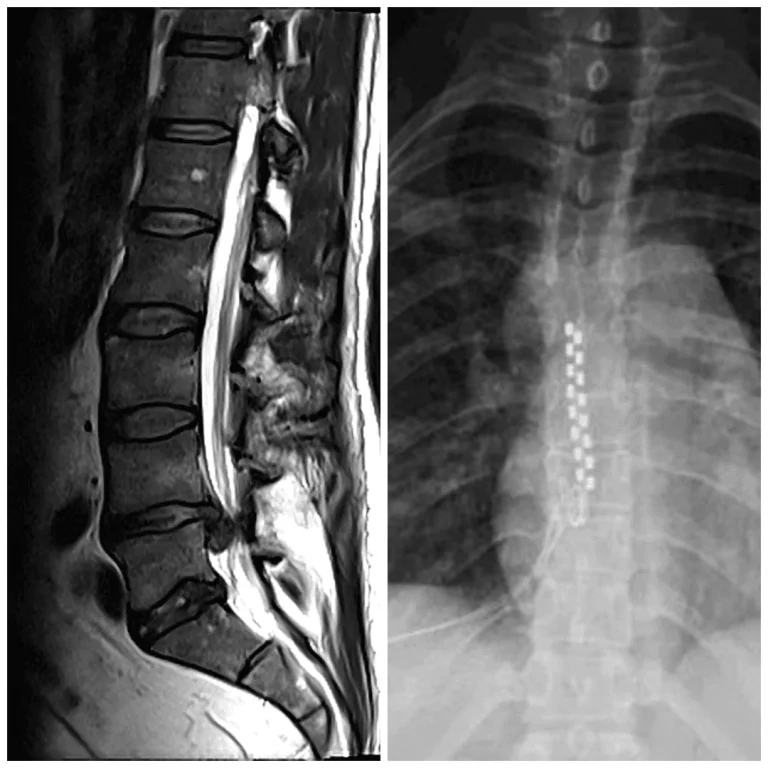

Spinal Instability

MRI and X-ray images of the spine showing hardware along the vertebral column.

X-ray showing a spinal cord stimulator with leads along the spine.

Lead Migration & Scar Tissue